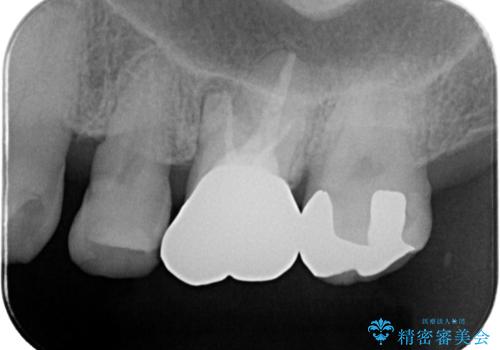

- 主訴:フロスを通したら、詰め物が取れた。適合の良いものを入れたい。

保険適用のメタルインレーが脱離しており、適合重視・咬合力が強いことからゴールドインレーでのやり替えとなりました。

フロスを通しインレーが脱離したことから、インレーと歯質との境に段差(適合不良)があった可能性があり、適合の良さや咬合力による補綴物の破折リスクを考慮し、ゴールドインレーでのやり替えとなりました。